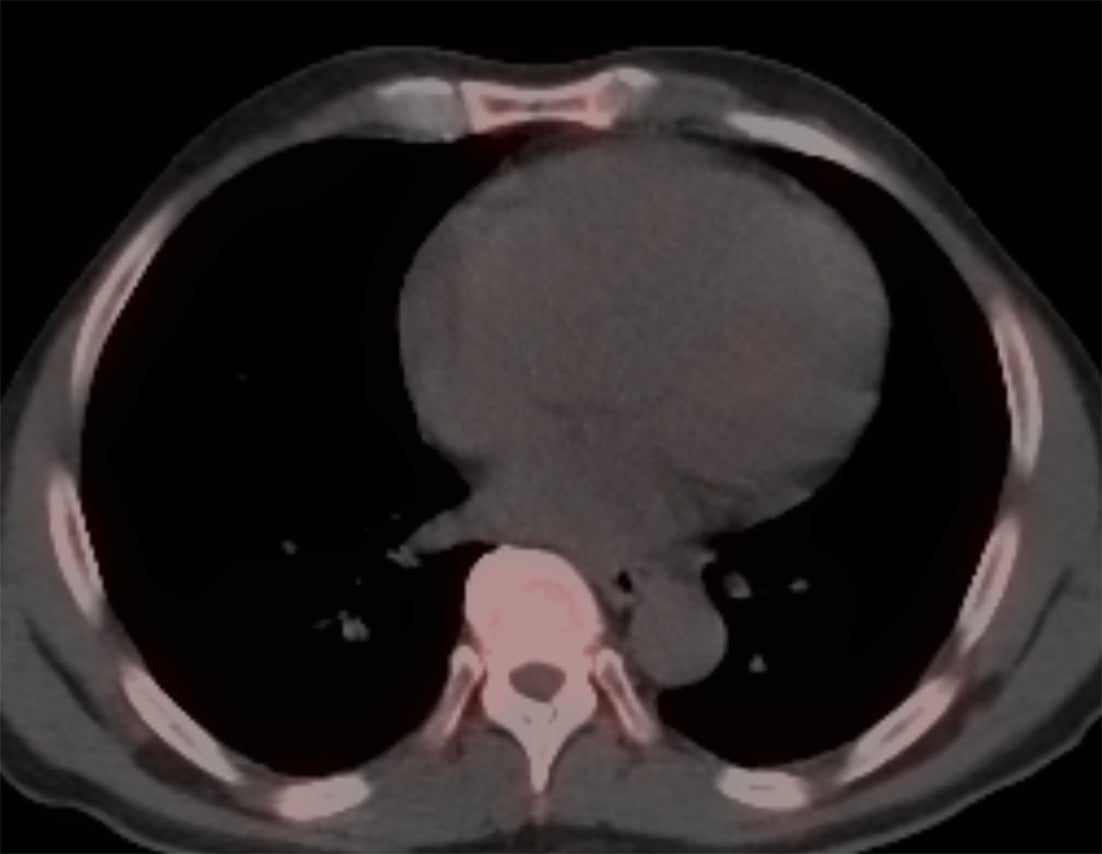

Perugini et al. in 2005 demonstrated that 99mTc-DPD (diphosphono-1,2-propanodicarboxylic acid) scintigraphy could noninvasively differentiate ATTR cardiac amyloidosis from AL amyloidosis with high accuracy.12 ATTR cardiac amyloidosis showed uptake for bone radiotracers, whereas AL cardiac amyloidosis showed minimal to no uptake ( Figures 1 , 2 ). They also developed the visual Perugini grading scale (0‐3) for semiquantitative assessment as below.12

SPECT/CT image of the chest without any myocardial uptake, ruling out the possibility of TTR amyloidosis.